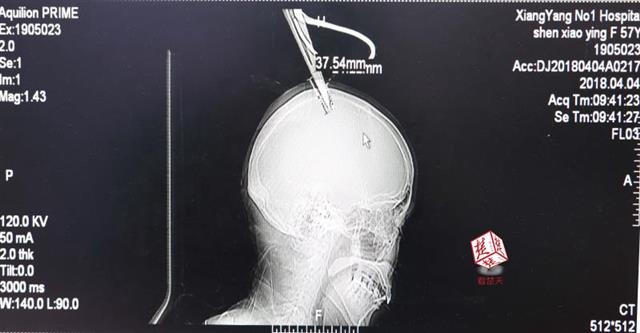

4月4日清晨,襄陽市樊城區太平店鎮57歲的農村婦女沈某,在采摘香椿嫩芽時,綁在竹桿上的剪刀因竹子腐朽不慎折斷,剪刀斜插入頭顱。經過及時搶救,目前脫離生命危險。

醫生檢查發現,剪刀刀尖斜嵌在沈某顱骨里,離腦髓只有兩三毫米。所幸是斜著插進去,如果是垂直刺入,很有可能造成癱瘓。

醫生檢查發現,剪刀刀尖斜嵌在沈某顱骨里,離腦髓只有兩三毫米。所幸是斜著插進去,如果是垂直刺入,很有可能造成癱瘓。最終經過手術,剪刀被取出,沈某目前仍在ICU進一步觀察。